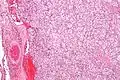

S100 immunostain highlighting the sustentacular cells in a paraganglioma

With immunohistochemistry, the chief cells located in the cell balls are positive for chromogranin, synaptophysin, neuron specific enolase, serotonin, neurofilament and Neural cell adhesion molecule; they are S-100 protein negative. The sustentacular cells are S-100 positive and focally positive for glial fibrillary acidic protein. By histochemistry, the paraganglioma cells are argyrophilic, periodic acid Schiff negative, mucicarmine negative, and argentaffin negative.